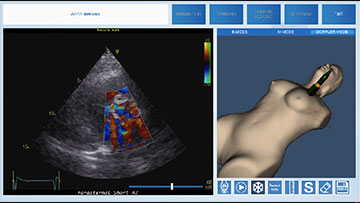

Симулятор ультразвуковой диагностики MedVision SonoVision

Виртуальный симулятор ультразвуковых исследований (УЗИ) SonoVision – обучающий тренажер на единой платформе обеспечивающий освоение основных навыков проведения ультразвукового исследования, понимание и идентификацию различных заболеваний и патологии внутренних органов человека.

SonoVision – симулятор ультразвуковой диагностики является инструментом для профессионального изучения медицины. Это виртуальный симулятор для отработки навыков ультразвуковой диагностики. Он используется как студентами, так и практикующими специалистами в клиниках и больницах. Симулятор ультразвуковой диагностики – прекрасное дополнение к традиционному обучению и повышению квалификации медицинского персонала.

Новое поколения симулятора УЗИ гарантирует высочайший уровень детализации внутренних органов, а работа с анатомически корректным манекеном обеспечивает реалистичные тактильные ощущения и визуальную картину при выполнении вмешательств. В симуляторе реализовано более 40 клинических сценариев.

Модуль по трансторакальному УЗИ сердца

- Обучающий модуль по трансторакальному ультразвуковому исследованию сердца